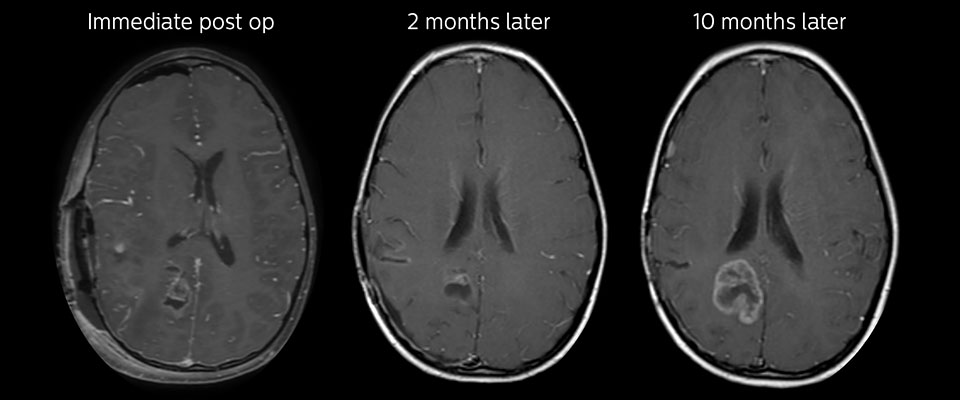

Eine MRT kann nach der Tumorresektion erfolgen, um auf Residualtumorgewebe oder erneutes Tumorwachstum zu untersuchen. Auch hier können die verschiedenen Kontrastmechanismen von APT die Diagnose unterstützen. Dr. Miller erinnert sich an einen bestimmten Fall. „Nach einer sehr guten Resektion sahen wir kleine Veränderungen auf den kontrastverstärkten T1-gewichteten und T2-gewichteten Bildern, die wie eine geringe Menge postoperativer Flüssigkeit aussahen. Interessanterweise sahen wir jedoch auch einen fokalen Bereich mit einem APT-Signal direkt in der Mitte der Anomalie. Wie immer, wenn wir ein wenig unsicher sind, führten wir weitere Untersuchungen durch und fanden leider neues Tumorwachstum in dieser Region“, so Dr. Miller. „Fälle wie dieser motivieren mich und andere, die sich um dieses Patientenklientel kümmern, zu untersuchen, wie dieses APT-Verfahren auf hohem Niveau für diese Patienten genutzt werden könnte und uns hilft, hochwertige diagnostische Informationen zu erhalten.“ Die Ärzte des Krankenhauses hatten auch einen Fall, in dem APT negativen Vorhersagewert hatte. Nach der Resektion eines hoch differenzierten Tumors gab es eine ähnliche geringfügige Veränderung auf den Bildern dieses Patienten. In diesem Fall war das APT-Signal jedoch ziemlich niedrig. In einem kürzlich durchgeführten Scan des Patienten wurde kein Rezidiv festgestellt.

MRT mit APT nach der Resektion

Unmittelbar nach der Resektion wurde erneut eine MRT durchgeführt. Die T2-gewichteten und kontrastverstärkten T1-gewichteten Bilder lassen keine eindeutige Unterscheidung von Residualtumorgewebe und postoperativen Gewebeveränderungen zu. Auf dem APT-Bild ist noch ein hohes Signal zu sehen, das auf Residualtumorgewebe hindeuten würde.

Nachuntersuchung im Laufe der Zeit

In späteren Nachuntersuchungsscans weisen die kontrastverstärkten T1-gewichteten Bilder auf rezidivierendes Tumorwachstum hin. Daher wäre es interessant, den prädiktiven Wert von APT in einer grossen Patientengruppe zu untersuchen.